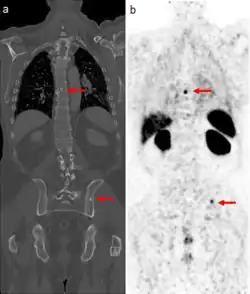

Gallium PSMA scan

The positron emitting isotope, 68Ga, can be used to target prostate-specific membrane antigen (PSMA), a protein which is present in prostate cancer cells. The technique has been shown to improve detection of metastatic disease compared to MRI or CT scans.[25]

In December 2020, the U.S. Food and Drug Administration (FDA) approved 68Ga PSMA-11 for medical use in the United States.[26][27] It is indicated for positron emission tomography (PET) of prostate specific membrane antigen (PSMA) positive lesions in men with prostate cancer.[28][27] It is manufactured by the UCLA Biomedical Cyclotron Facility.[27] The FDA approved 68Ga PSMA-11 based on evidence from two clinical trials (Trial 1/NCT0336847 identical to NCT02919111 and Trial 2/NCT02940262 identical to NCT02918357) of male participants with prostate cancer.[27] Some participants were recently diagnosed with the prostate cancer.[27] Other participants were treated before, but there was suspicion that the cancer was spreading because of rising prostate specific antigen or PSA.[27] The trials were conducted at two sites in the United States.[27]

The FDA considers 68Ga PSMA-11 to be a first-in-class medication.[29]

Gallium PSMA scanning is recommended primarily in cases of biochemical recurrence of prostate cancer, particularly for patients with low PSA values, and in patients with high risk disease where metastases are considered likely.[30][31]

An intravenous administration of 1.8–2.2 megabecquerels of 68Ga PSMA-11 per kilogram of bodyweight is recommended. Imaging should commence approximately 60 minutes after administration with an acquisition from mid-thigh to the base of the skull.[30][32]